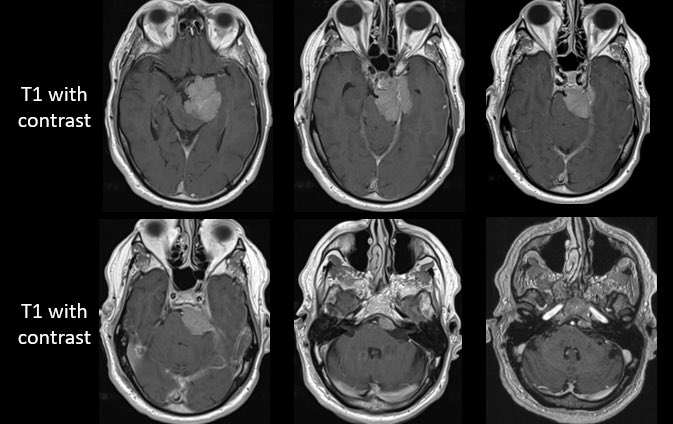

How would you manage this 42F w/ intracranial recurrence of optic nerve sheath meningioma initially biopsied at OSH 5 yrs ago. R eye blind, L 20/20, EOMI. Observation? Radiation? If surgery, approach/extent of resection? #Neurosurgery #MedEd #MedTwitter @EvaWuMD @TheJNS @WFNSHQ